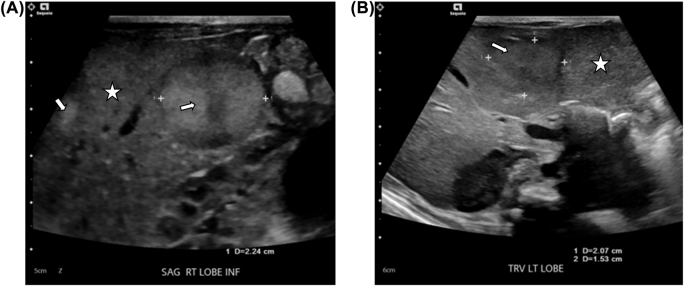

Case presentation: A 24-day old preterm 32 weeks' gestation male neonate developed cholestasis that lead to the diagnosis of stage MS neuroblastoma. There was no NB primary site identified.

Conclusions: To the best of our knowledge, this is the first case report of metastatic NB (Stage MS) in a preterm neonate presenting with cholestsis but without any identifiable adrenal or extra-adrenal primary.